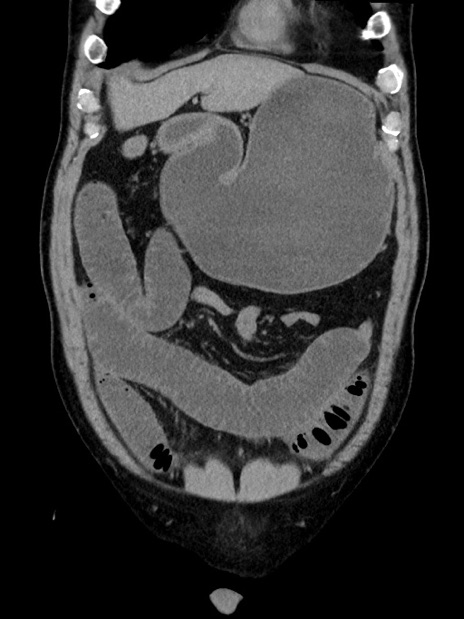

症例35(冠状断像)

【症例】70歳代 男性

【主訴】腹部膨満、嘔吐

【現病歴】昨日より腹部膨満感出現。本日増悪し、仙痛出現。嘔吐あり、受診。

【既往歴】糖尿病、胆摘後

【身体所見】BP 149/80mmHg、HR 74/min、BT 35.9℃、腹部:膨満、軟、圧痛なし。腸雑音減弱あり。上腹部正中切開瘢痕あり。

【データ】WBC 13500、CRP 1.72